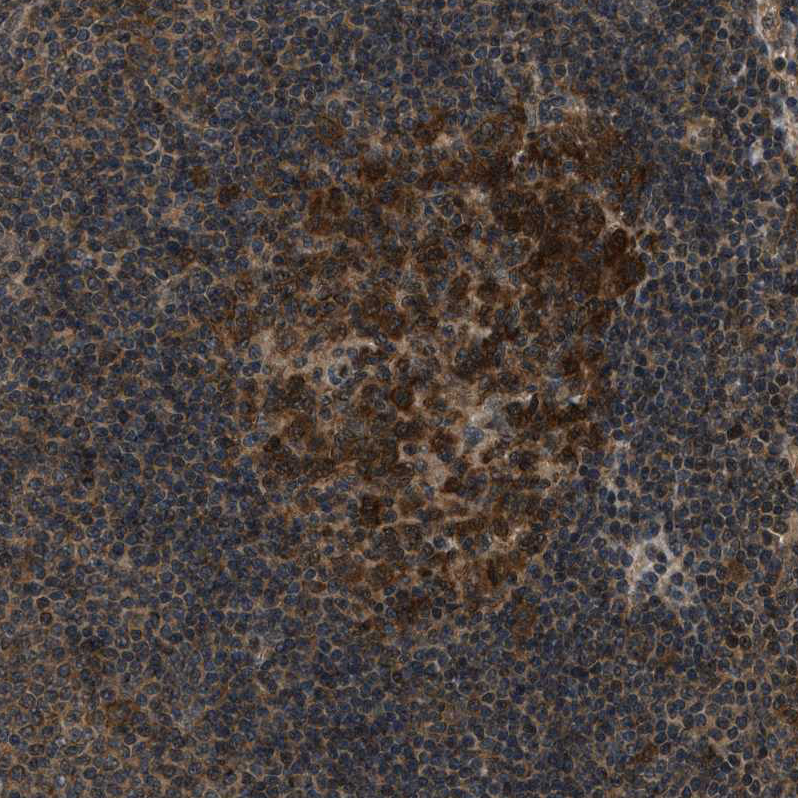

Immunohistochemical staining of human cerebral cortex, liver, lymphoid tissues and testis using Anti-NUDCD3 antibody HPA019528 (A) shows similar protein distribution across tissues to independent antibody HPA019136 (B).